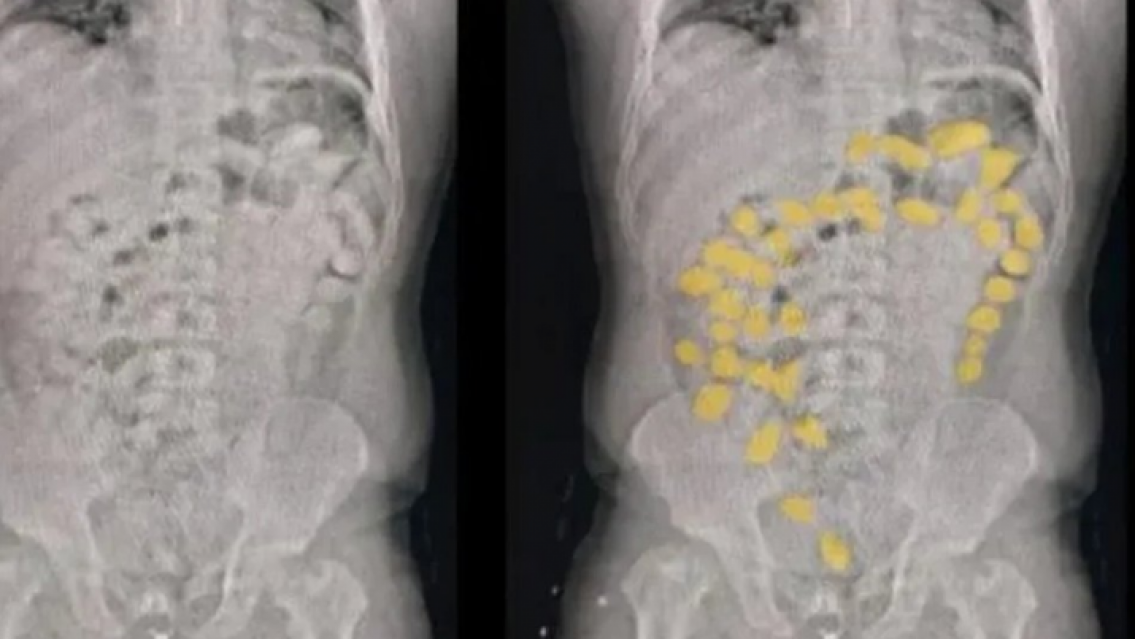

De acuerdo a las fuentes cercanas a la investigación, en el nosocomio los dos sospechosos fueron asistidos con el protocolo de evacuación para estos casos. Primero, les realizaron ecografías para contabilizar las cápsulas que se encontraban en el organismo. Y luego, comenzó el trabajo de expulsión de las mismas, de las cuales se habían contabilizado 187, informa El Tribuno.